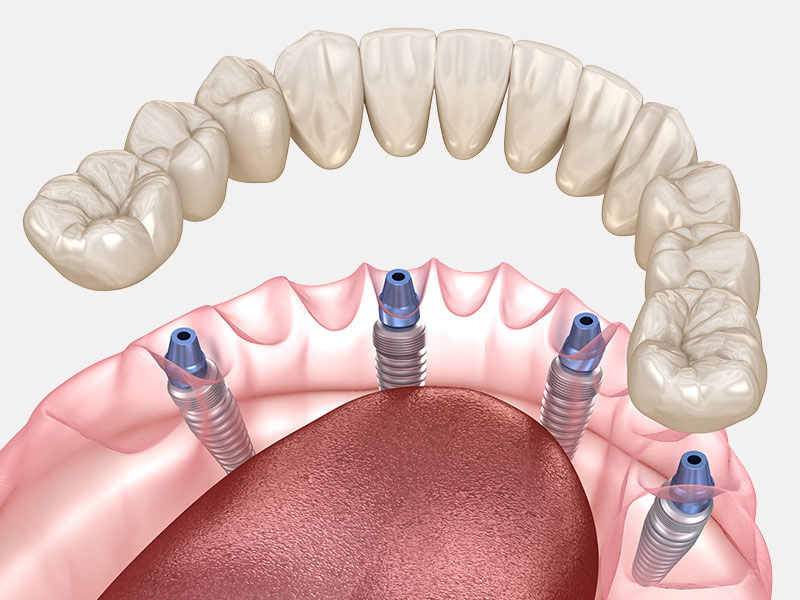

FULL-ARCH ALL-ON-4/6 IMPLANTS

Full-arch All-on-4/6 implants are revolutionary dental procedures designed to restore a fully functional and aesthetically pleasing smile to patients with extensive tooth loss or severe dental problems. The technique involves the strategic placement of four or six dental implants in the jawbone, providing a strong foundation for a fixed prosthetic bridge. These titanium implants fuse with the natural bone over time through a process called osseointegration, ensuring remarkable stability and durability. One key advantage lies in their ability to support an entire arch of teeth using just a few strategically positioned implants, minimizing invasive surgery and reducing healing time compared to traditional individual implant treatments. This innovative approach not only enhances oral function by allowing patients to enjoy eating all types of food but also significantly improves their quality of life by restoring confidence in their appearance.